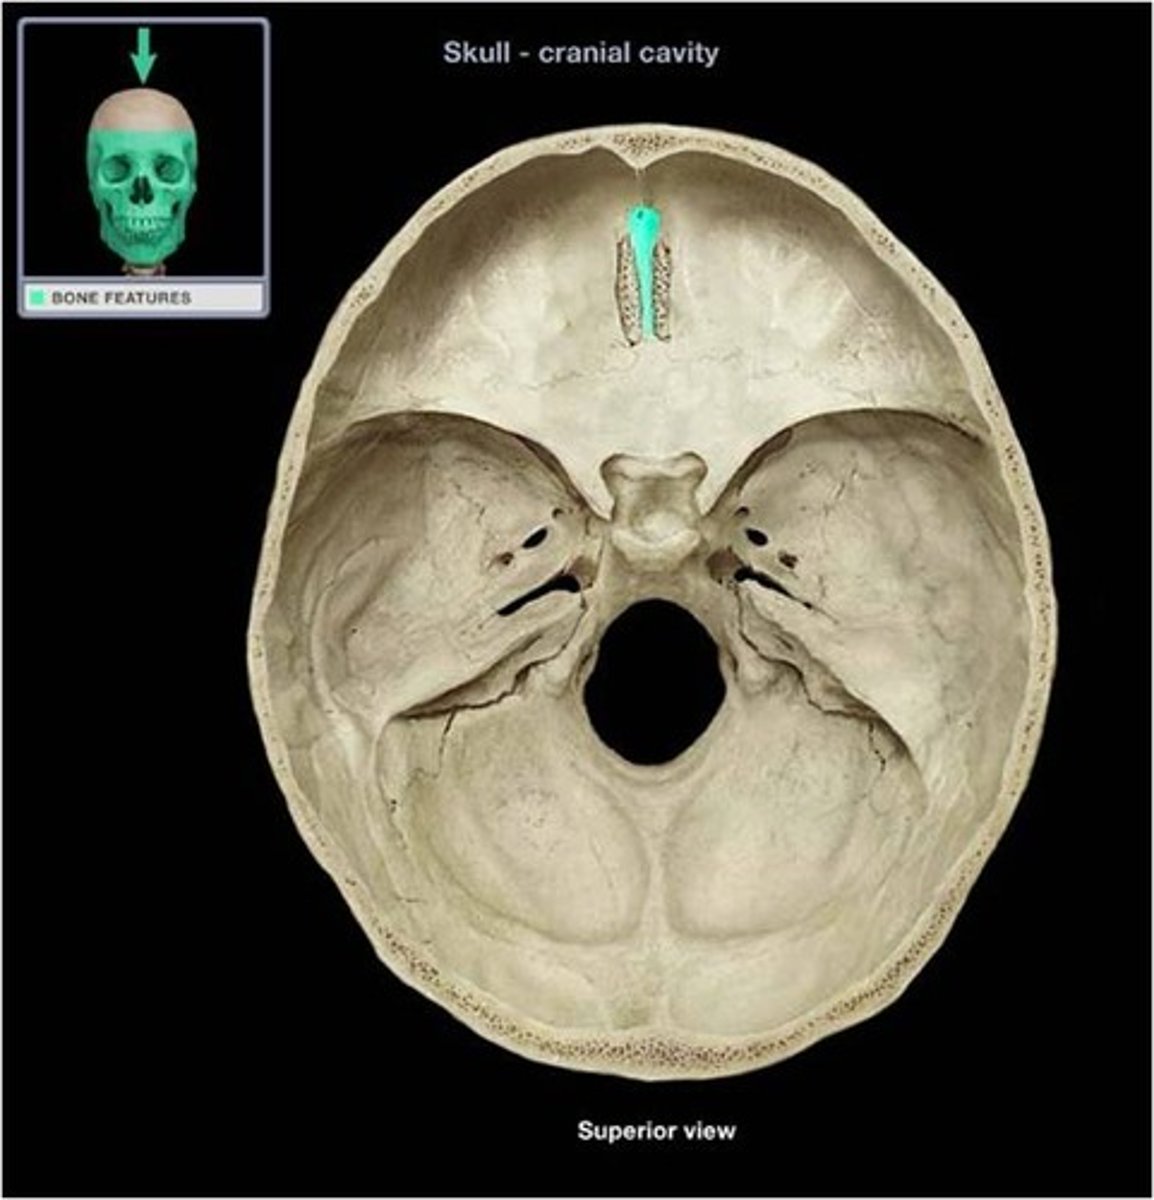

cribiform plate

Name this structure.

crista galli

Name this structure.